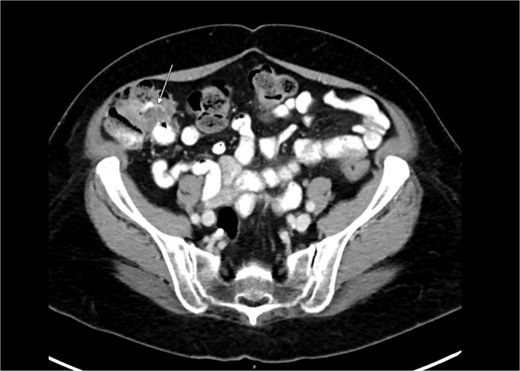

Diagnostic laparoscopy demonstrated multiple cystic lesions throughout the abdomen and pelvis (Figs 3 and 4). The gross appearance of these cysts was consistent with mucinous carcinomatosis. Laparoscopic excisional biopsy of several lesions was performed. Frozen section analysis revealed mucin but did not reveal evidence of metastatic adenocarcinoma. Colectomy was deferred due to concern for carcinomatosis, as if confirmed, she would likely be treated with neoadjuvant chemotherapy, restaging, followed by cytoreductive surgery (to include synchronous right colectomy) with heated intraperitoneal chemotherapy.

Intraoperative view of the right lower quadrant of the abdomen: cysts involving peritoneum of the right colon and mesentery.